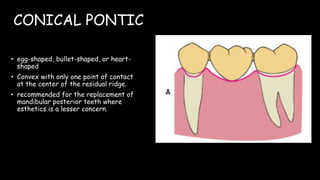

The document discusses pontic design for fixed dental prostheses. It covers pretreatment assessment of residual ridge contours, classifications of ridge deformities, surgical modification techniques, and ideal requirements for pontics. Pontic designs are classified based on their shape and materials. Factors in pontic selection include esthetics and oral hygiene. Common designs for anterior and posterior regions are described, including sanitary, ovate, and saddle pontics. Biological considerations for pontic design involve maintaining the residual ridge, abutment teeth, and supporting tissues.

![PONTIC DESIGN CLASSIFICATION

• According to Rosenstiel

A] MUCOSAL CONTACT:

1. Ridge lap

2. Modified ridge lap

3. Ovate

4. Conical

B) NO MUCOSAL CONTACT

1. Sanitary (hygienic)

2. Modified sanitary (hygienic)](https://image.slidesharecdn.com/ponticandponticdesigns-201011153902/85/Pontic-and-pontic-designs-23-320.jpg)